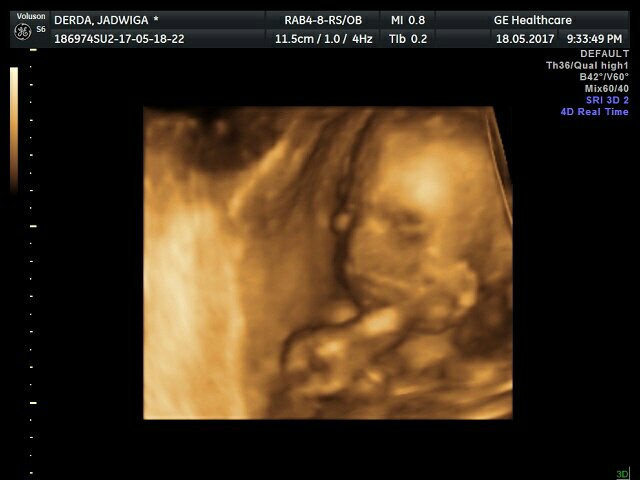

1495194458-aaaaaa.jpeg

Trochę zmienił położenie ale jest mocno wtulony w łożysko i ciężko było zrobić ładne zdjęcia ale coś się udało.

1495194514-aaaaaa.jpeg

1495194530-aaaaaa.jpeg

Najlepsze jest to, że według Polskich pomiarów jest mniejszy ale w normie więc się nie martwię.